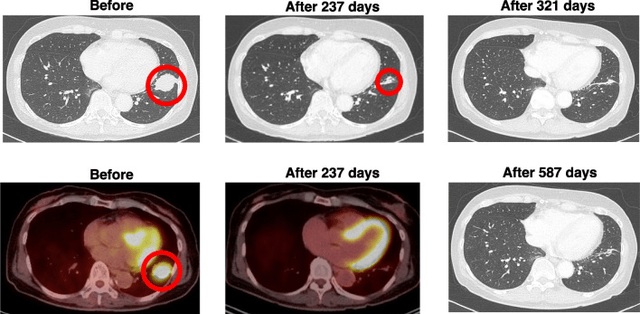

肺癌:DC疫苗联合方案实现肿瘤完全消失

一名63岁的EGFR突变肺腺癌患者,既往未接受过化疗。在接受厄洛替尼治疗约一个月的时间后,患者在继续服用厄洛替尼的基础上联合了树突状细胞疫苗。值得注意的是,在接受8剂WT1/MUC1-DC疫苗与厄洛替尼联合治疗237天后,肿瘤体积显著缩小至12毫米,降幅达65.7%。基于观察到的积极疗效,患者主动要求将厄洛替尼剂量减少,在治疗开始后第321天CT扫描未再检出肺癌病灶。患者在接种15剂WT1/MUC1-DC疫苗的过程中均未记录到任何不良反应。肿瘤消失的这一状态至少在治疗开始后587天内持续得到验证,期间未出现复发或转移迹象(2017年12月至2019年11月)。